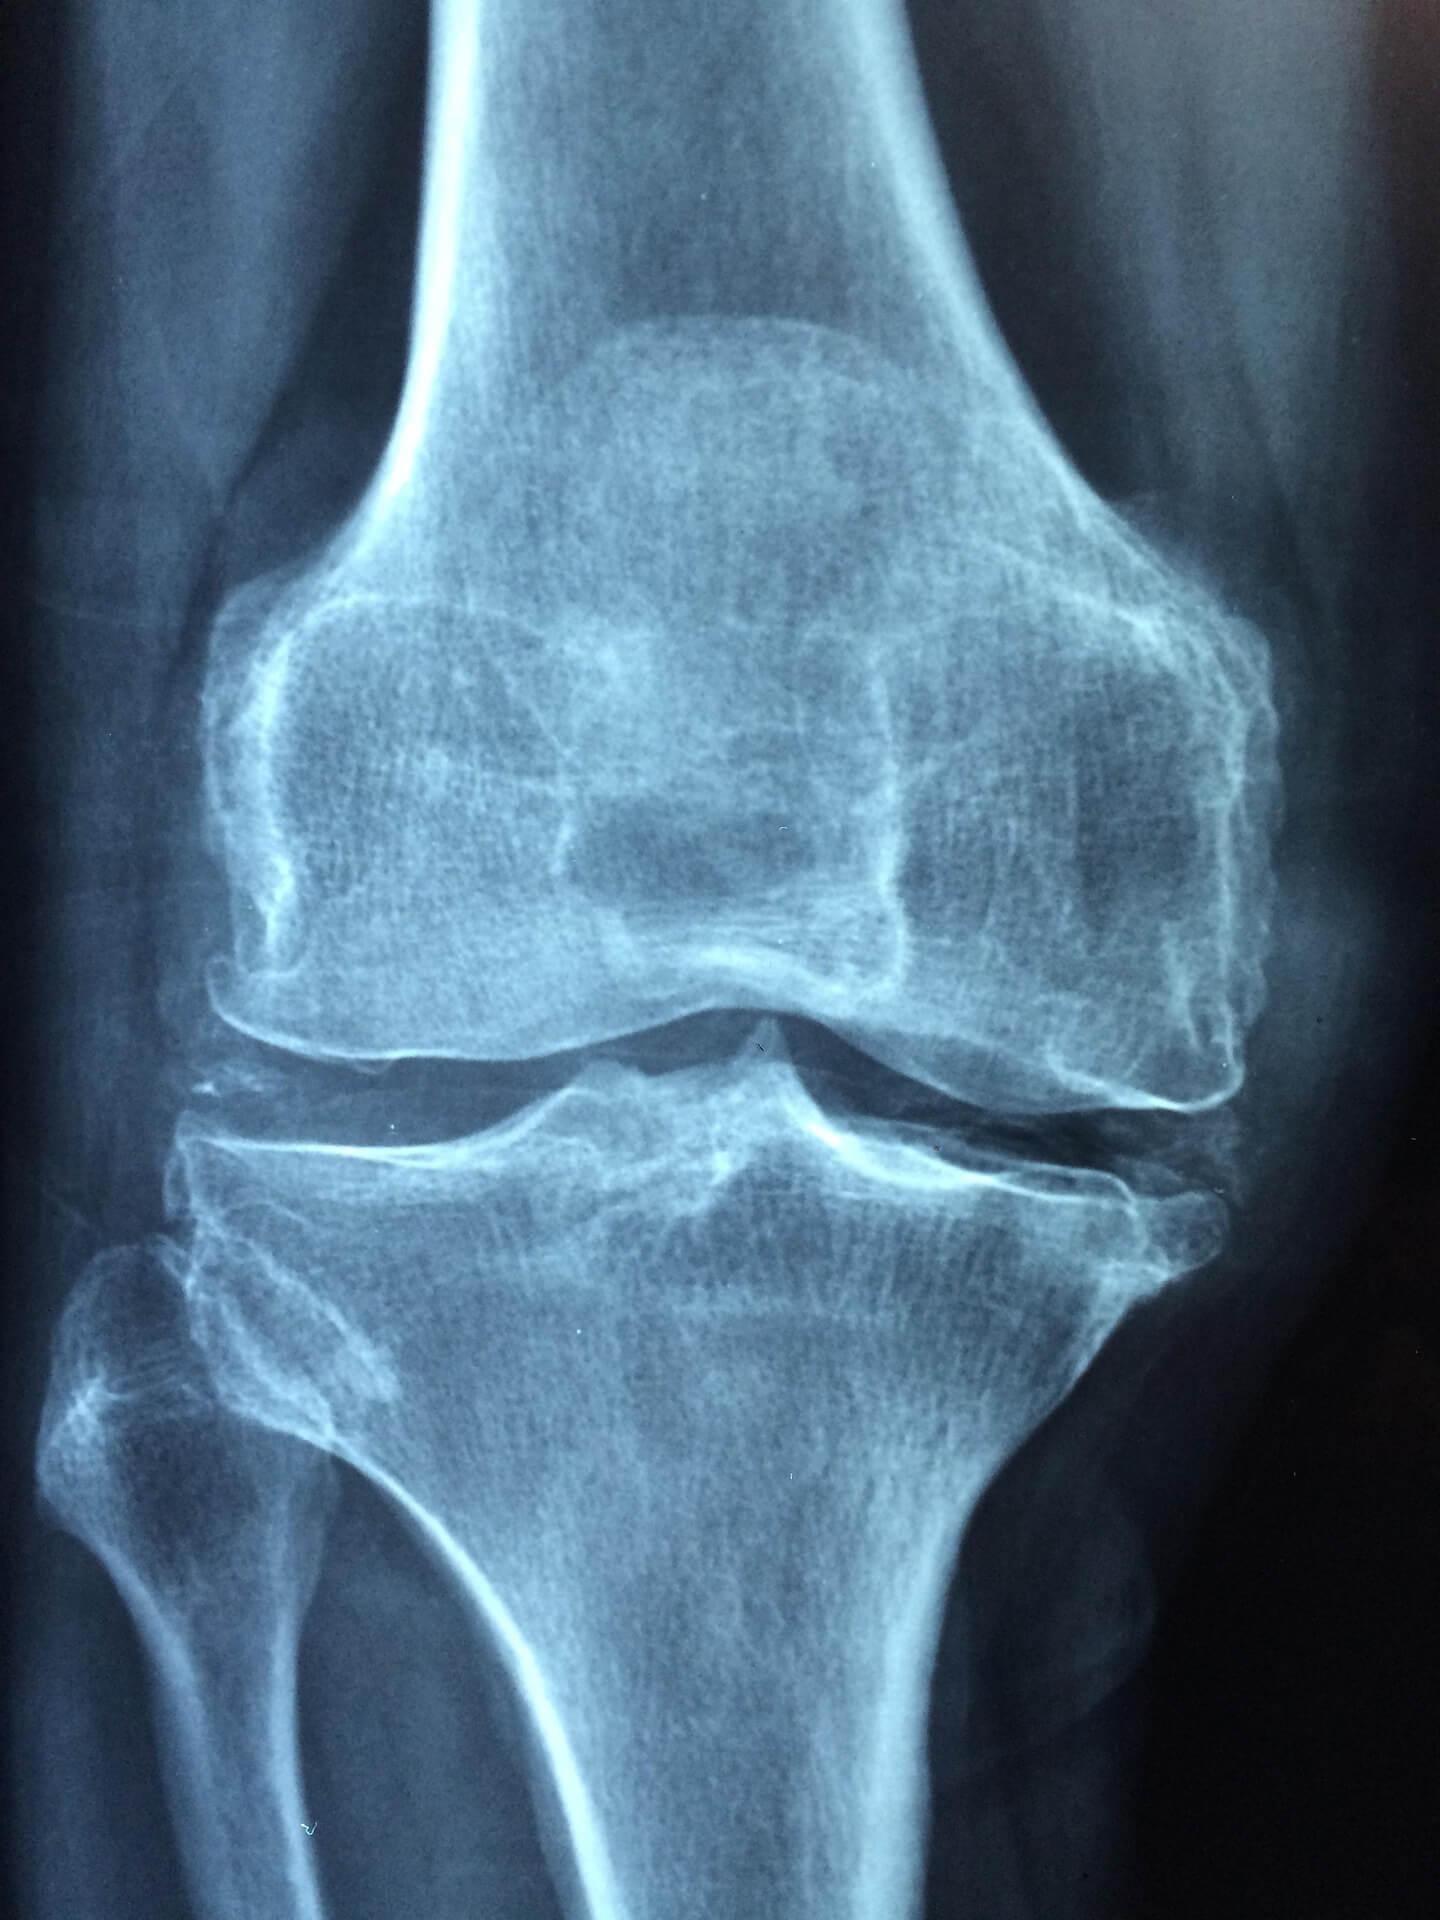

1. 무릎 통증의 원인과 관절의 구조 이해

1-1. 노화와 연골 손상

무릎은 인체에서 가장 큰 하중을 받는 관절입니다. 노화로 인해 연골이 점차 마모되면 관절액의 윤활 기능이 떨어지고, 이로 인해 통증이 발생합니다.